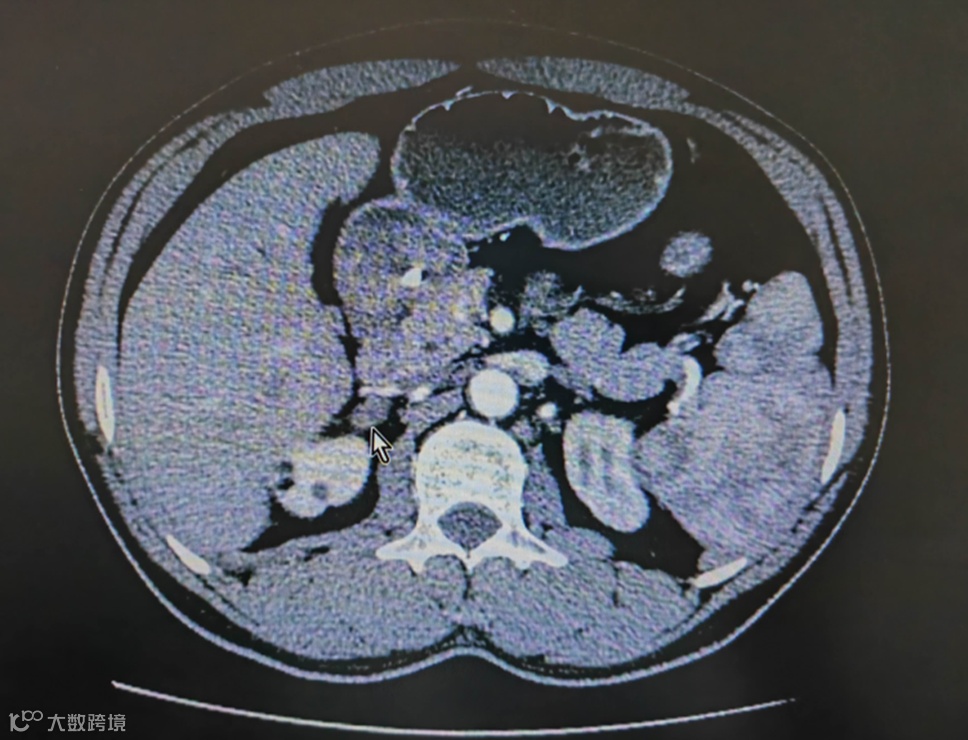

原来,他血液里肾上腺的激素水平远超正常值,CT提示右侧肾上腺长了一个不到2cm的肿瘤,他的高血压、乏力等症状很可能都是这个肿瘤在作怪,在进一步检查及充分的术前准备后,泌尿外科张宇主任为他安排了微创手术切除了肿瘤,手术后徐先生的血压慢慢降了下来,之前升高的激素也恢复到了正常的水平,顺利出院后他如愿购买了保险。